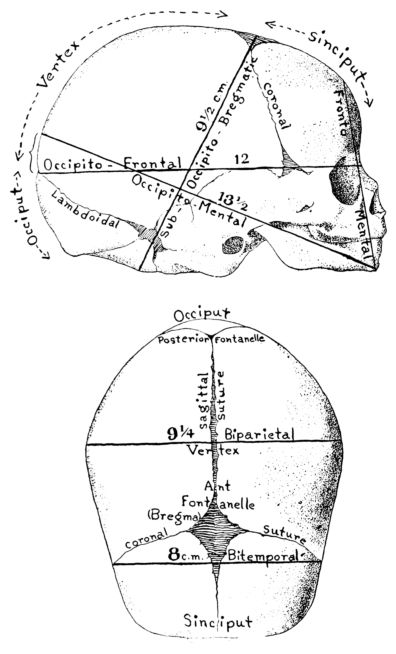

| 30. | Side and top view of fetal skull | 90 |